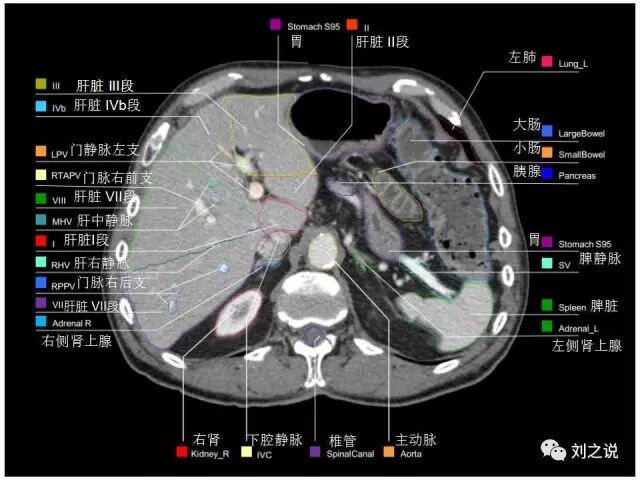

【解剖】高清实用 腹部CT断层

参考RTOG共识和3D-body解剖。